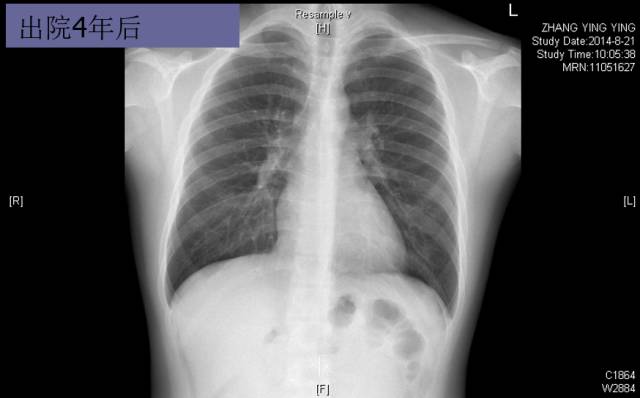

随访转归

► 7月后复查:心脏缩小,心功能好转

► 2年后病情平稳,复查超声心动图、NT-proBNP等大致正常。仅口服比索洛尔10mg qd+贝那普利5mg qd

► 3年后复查HOLTER:频发房早32925次,短阵房速。 患者心率控制在70-90bpm,超声心动图依然大致正常。未再出现胸闷,浮肿等症状。

► 6年内多次复查,UCG正常。无心衰症状。

► NT-proBNP 8787.94pg/ml(入院时)→540.1pg/ml(1年后)→ 378.4pg/ml(2年后),后多次复查均正常